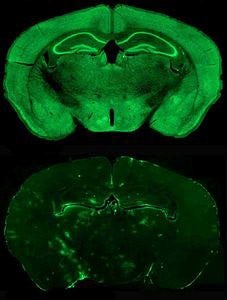

In a paper published in Nature Communications, Janet Berrios, a graduate student in the Philpot lab, discovered that the loss of UBE3A decreases the release of the GABA neurotransmitter and alters reward-seeking behavior in an important neural pathway once presumed to be principally regulated by the dopamine neurotransmitter.